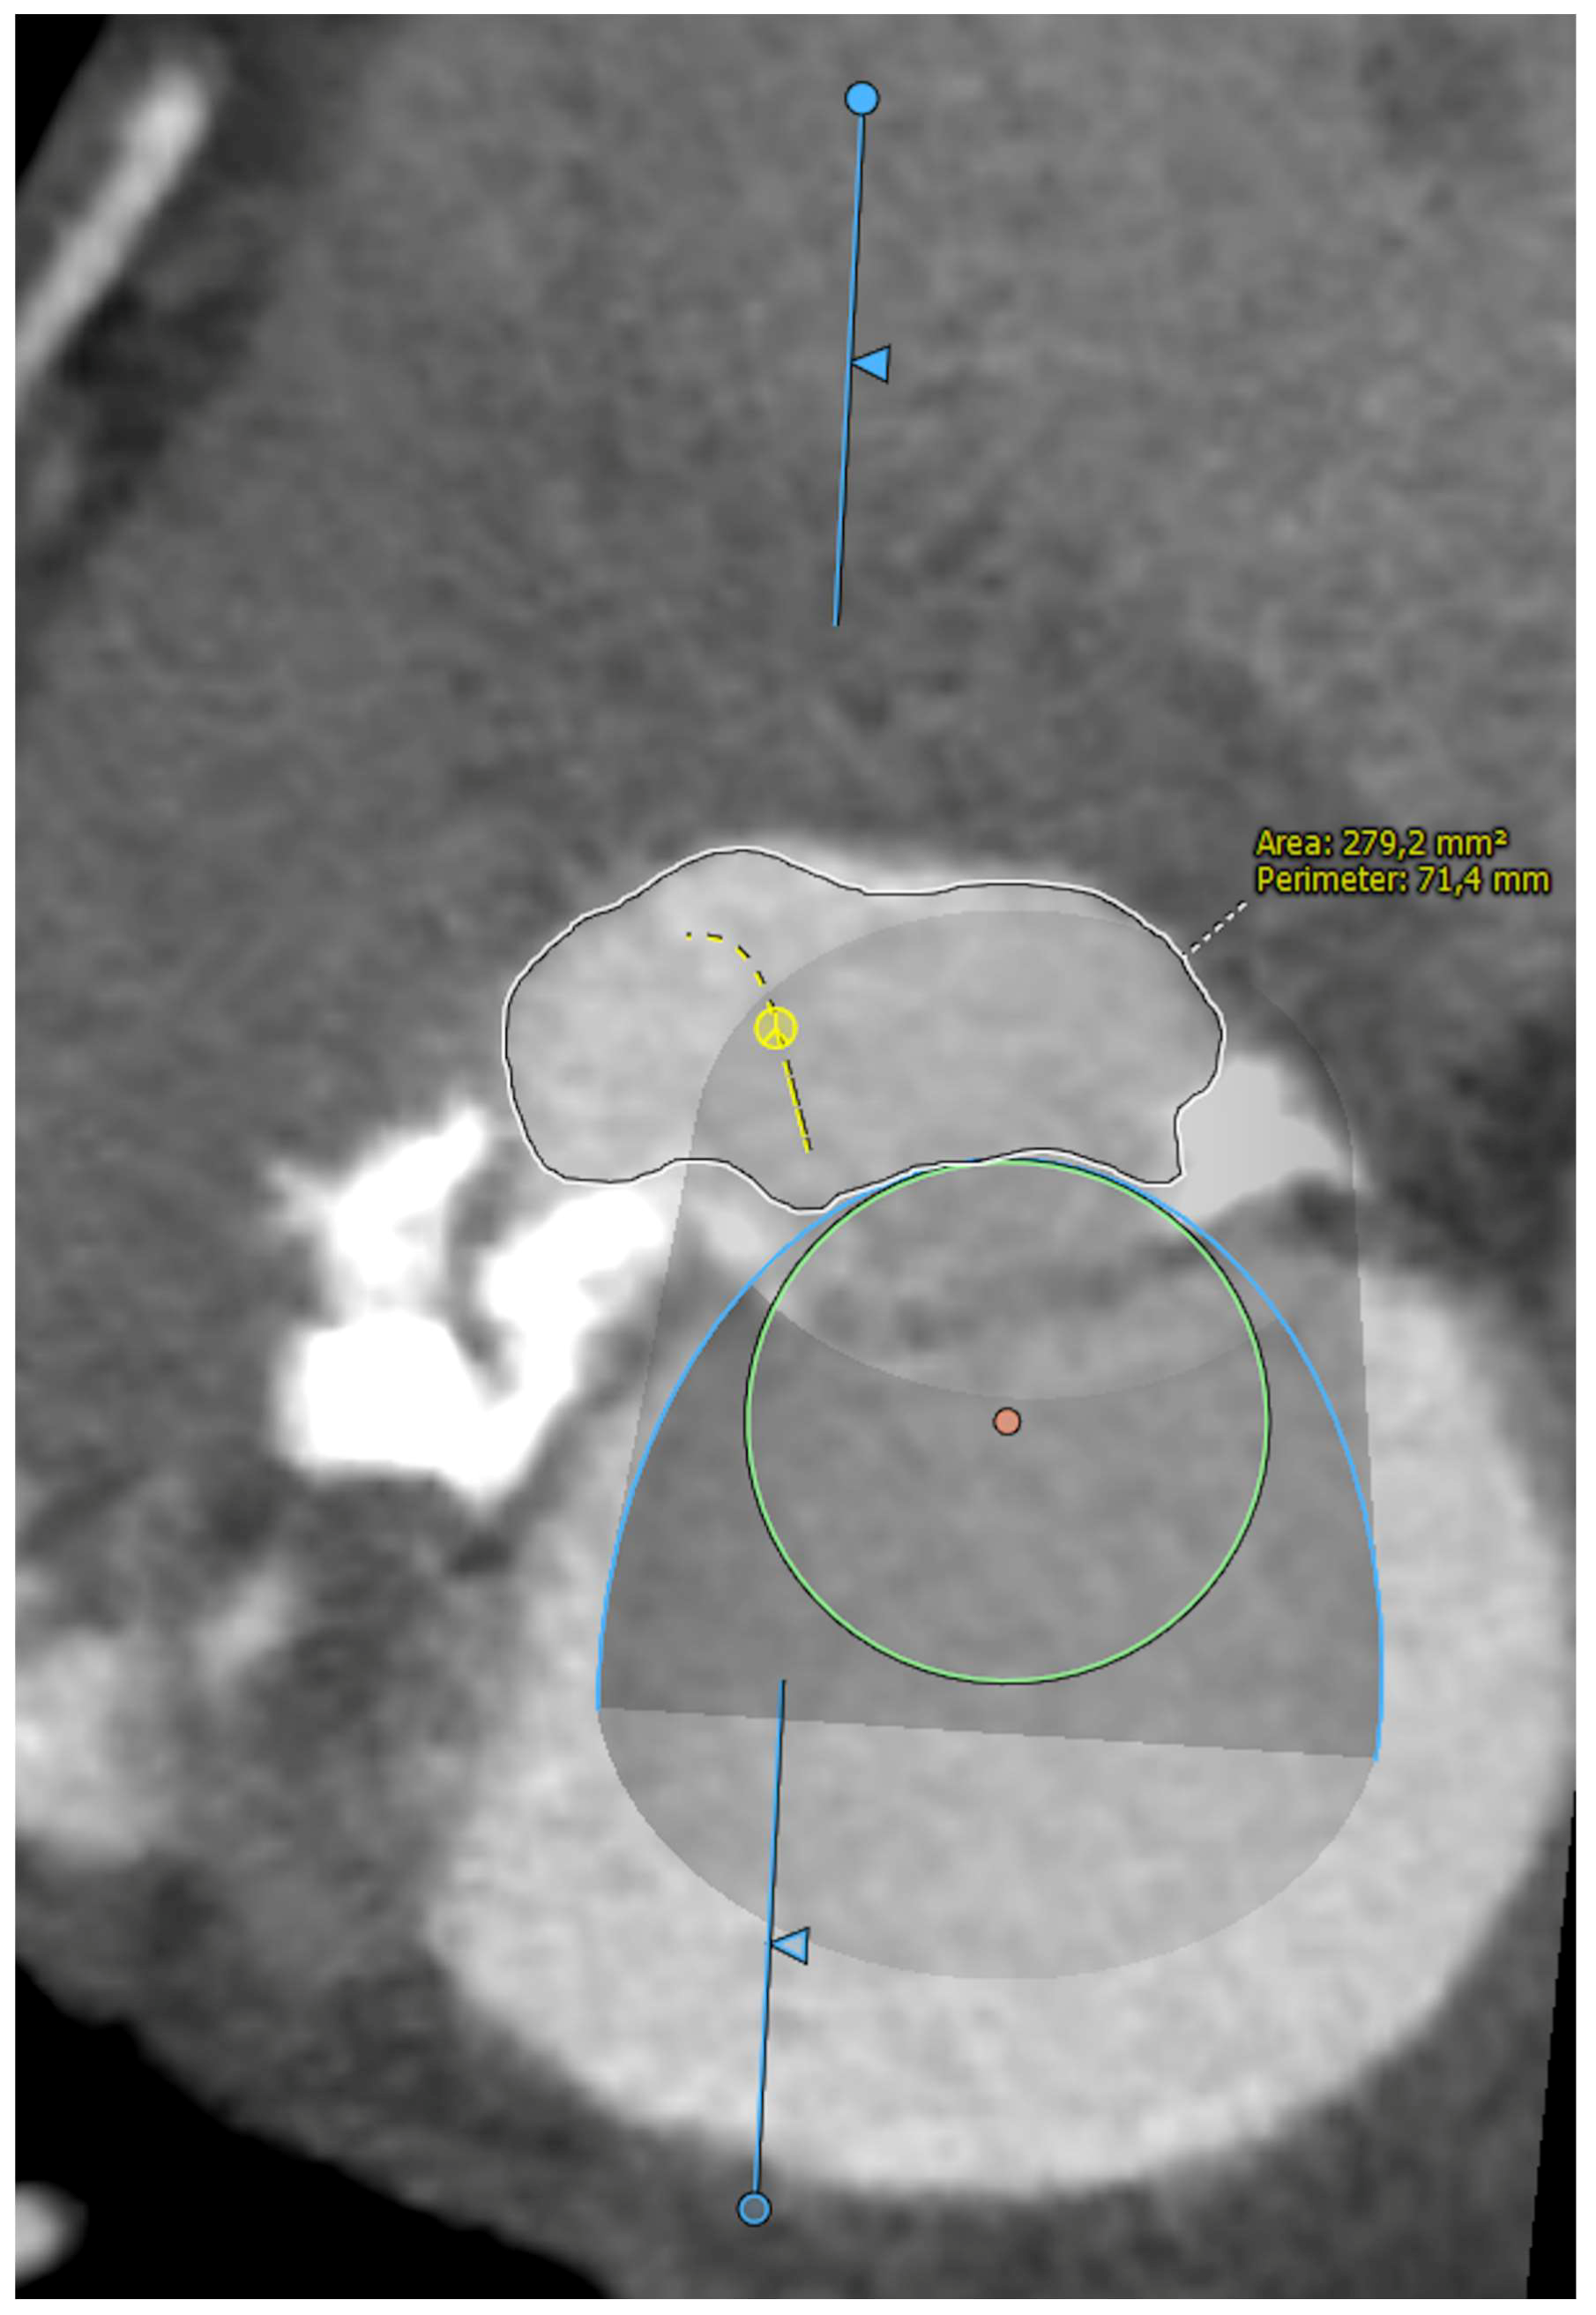

Five observational studies have been published since 2017 exploring the safety and efficacy of ViMAC, all of them with aortic balloon-expandable bioprosthesis in prohibitive surgical risk patients [17,18,19,20,21]. Their designs and main results are summarized in Table 1. To note, the ViMAC procedure shows worse results in terms of technical success and short- and mid-term outcomes than those of ViV and ViR. Indeed, ViMAC is the most challenging percutaneous scenario of all types of TMVR. Mortality at the one-year follow-up is high (around 50%), underscoring the importance of patient selection and of performing these interventions in experienced centers. When comparing the three approaches of TMVR for ViMAC, transatrial appears to have the best results, with one-year rates of mortality at 35% (25% in the latest series) [16,22,23], compared to those of transapical (57%) and transseptal (63%), and higher technical success rates (89% vs. 71% and 65%, respectively). The most important adverse event is the obstruction of the LVOT, with a hazard ratio for mortality of 2.87 (95% confidence interval 1.66–4.96) [19], so this must always be anticipated by a preprocedural CT. An area below 170 mm2 in the LVOT once the valve is implanted (“neo-LVOT”) is highly predictive of this complication (Figure 6) [13]. Other important CT parameters include the angle between the aorta and the LV axis (Figure 7), mitral annulus dimensions (Figure 8), and 2D- or 3D-derived virtual reconstructions (Figure 6).

Figure 6.

“Virtual” valve reconstruction (blue line) and neo-left ventricular outflow tract measurements.

Figure 7.

Angle between the aortic and the left ventricular centerlines (aorto-mitral angulation, 53o), predictive of left ventricular outflow tract obstruction.

Figure 8.

Assessment of mitral annular dimensions and grading of calcium.